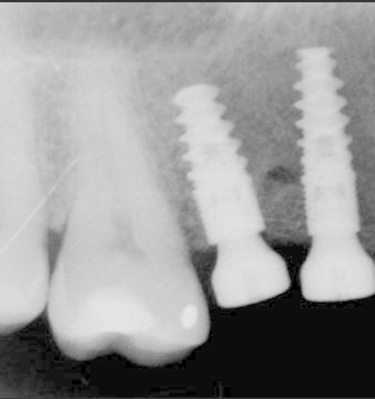

4.Colocación del implante: Realizada por un especialista en un cirugía.

5.Osteointegración: El implante debe fusionarse con el hueso y estabilizarse aprox. 3-6 meses